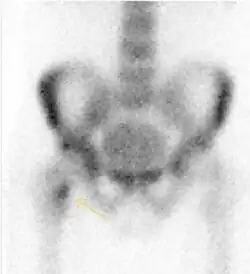

MRI has been shown to have 100% sensitivity and specificity in prospective studies of occult hip fractures. These fractures were diagnosed by bone marrow edema and a low signal fracture line, mainly on T1 or T2 weighted images (Figure 10).[1]

Figure 10:

-

Stress femoral neck fracture in a young athlete barely visible in X-ray film as a sclerotic line (arrow)[1] -

In this case, Tc 99 scintigraphy shows a band of uptake[1] -

Furthermore, T1 (left) and DP fat saturated (right) weighted MR images showed the fracture line and a pattern of edema.[1]

Nuclear Medicine

Bone scanning in people with hip pain can be complementary to other imaging studies, mainly in indeterminate bone lesions to clarify whether it is an active lesion with abnormal radiotracer accumulation. Nevertheless, MRI has replaced scintigraphy in the diagnosis of most of these conditions. An example is stress or insufficiency fractures: increased uptake is usually present in around 80% of fractures within 24 h, and 95% of fractures reveal activity by 72 h following trauma, showing an overall sensitivity of 93% and specificity of 95%. MRI is superior to bone scans in terms of sensitivity (99%-100%) and specificity (100%). Moreover, a bone scan does not provide detailed anatomical location of the fracture, and further imaging is usually required.[1]